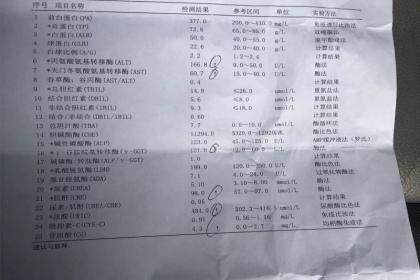

武汉惠鑫健康管理有限公司专业代开上海医院病历证明17267193882,诊断证明,医院病假条、病假单、请假条、病例单,医院休学证明、免军训证明、免体测证明,化验单、CT报告单、B超单、病理报告、心电图,三甲医院病例诊断证明、医院住院证明、医院出院证明,医院怀孕证明、结扎上环证明、流产引产证明,医院病危通知书、医院全套病历等等。长期与市区各大三甲医院保持良好关系,欢迎随时联系我们!

医院病假单主要就是由医生开取的一个关于身体的病状情况,在严重的情况下要请假休息才行。很多人在请假的时候不知道怎么开医院病假条,请直接联系我!只有写好医院请假条才能使自己在家里安心养病,休假也是为了自己的身体健康尽快恢复。医院一般不可以直接开病假条,但是经正规医院的医师检查后,可以为病人开具疾病诊断书、健康证明书等材料,而劳动者可以携带该材料去申请用人单位开病假条。

总之,现在很多情况都会要求开具各种各样的医院病历证明,譬如公司请病假,怀孕休假,学校办休学,免军训,免体免测等等。什么情况才能开具诊断证明?复杂也好,难办也好,放轻松一点,我们愿意为您代劳!